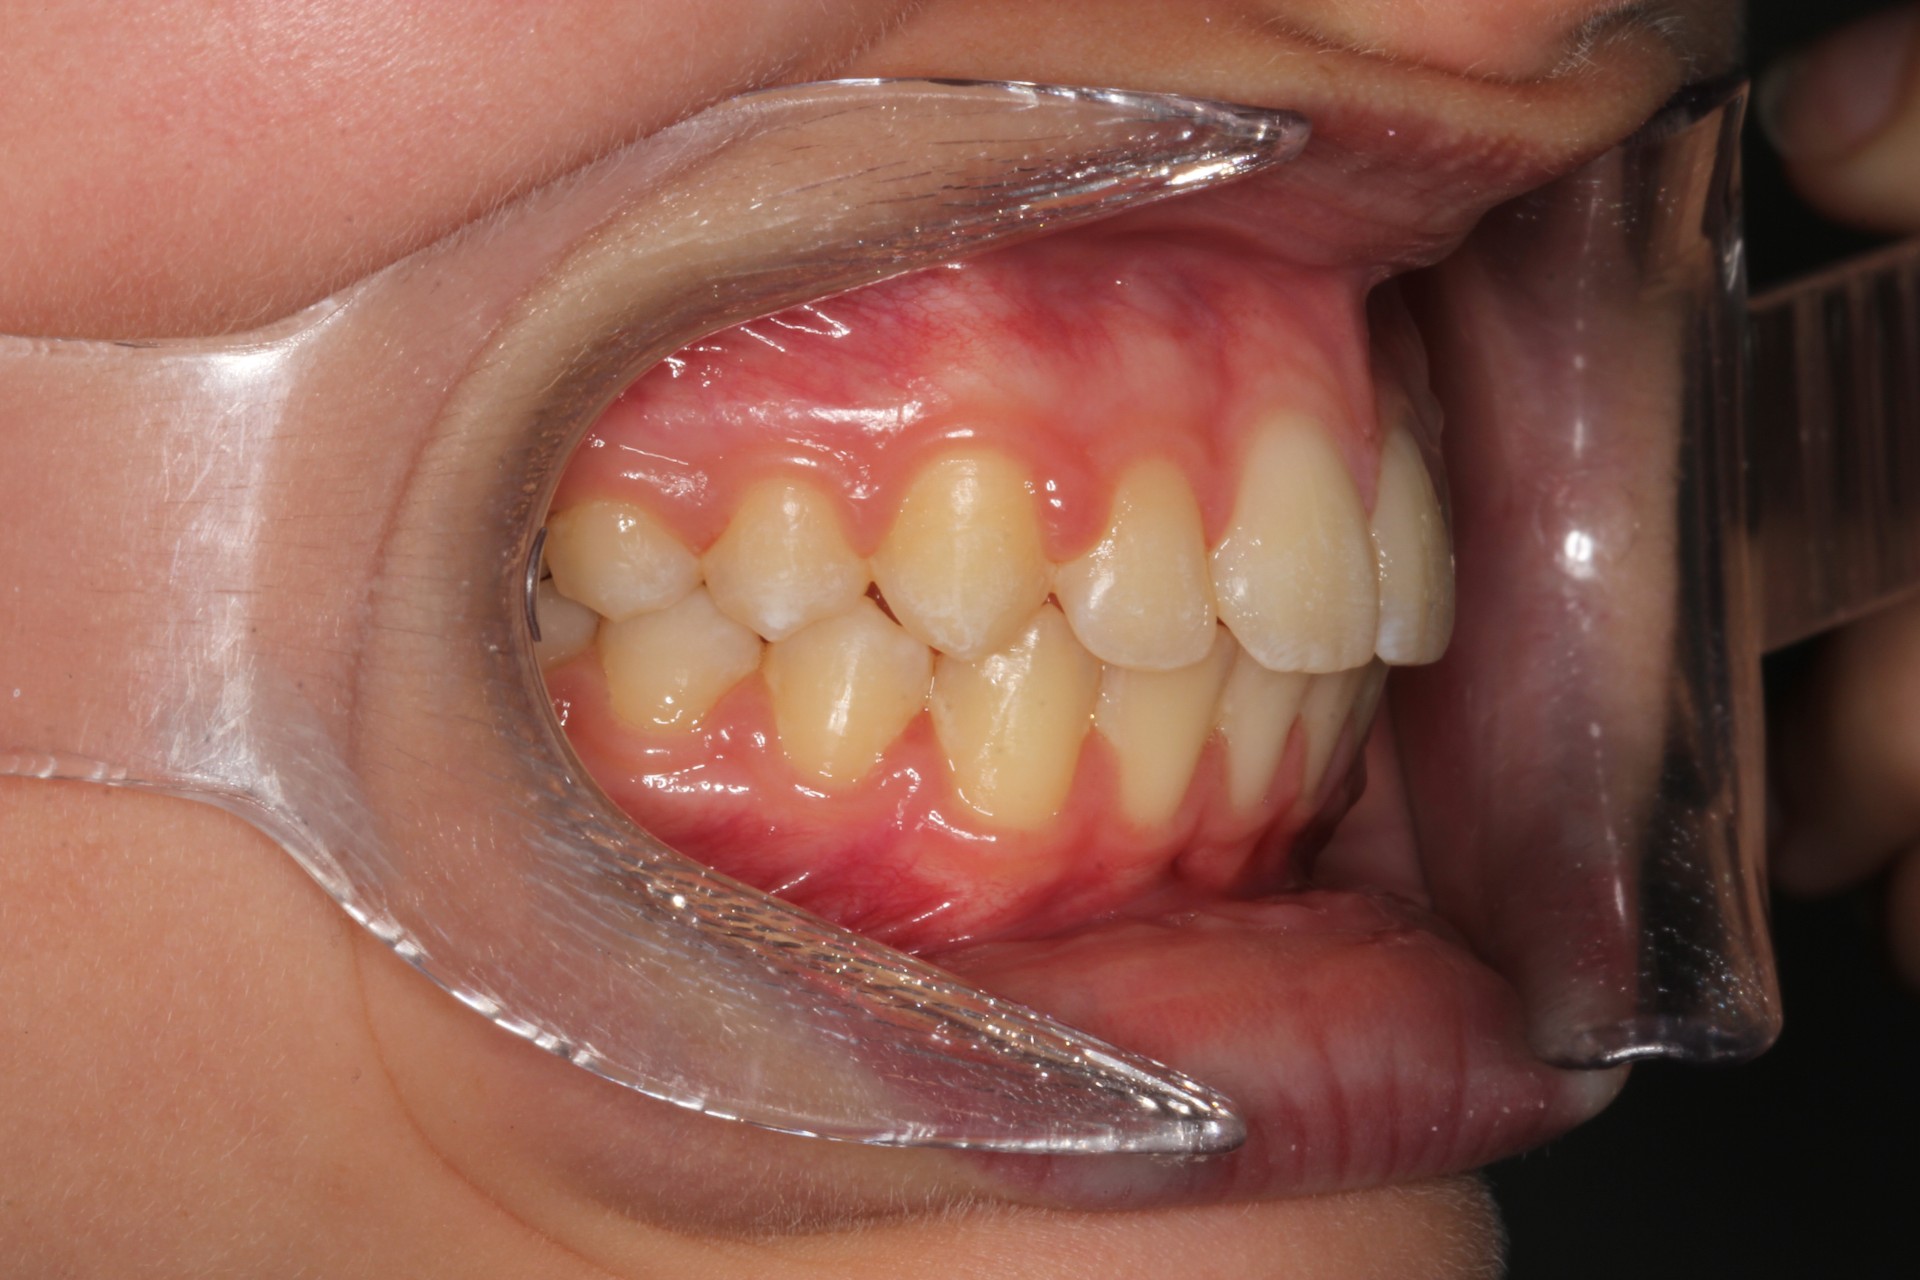

Protruding front teeth – Child case

Protruding front teeth and spacing – Child case

Protruding front teeth with midline diastema – Child case